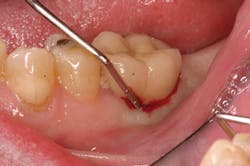

Late implant complications occur after the implant has integrated and the final prosthesis has been placed. Recognition of these complications via radiographic and clinical analysis is extremely important since many of these problems can be corrected if detected early. On the other hand, if allowed to progress, a minor complication can often result in loss of the implant and/or prosthesis. Late complications of the dental implant fall into the category of biologic or mechanical complications. Late biologic complications are those in which the peri-implant soft and hard tissues are affected. Peri-implant mucositis describes a reversible inflammatory reaction in the mucosa adjacent to an implant,(8) a term that has become known as implant gingivitis. Studies show that the prevalence of peri-implant mucositis can be as high as 50% to 80% of implants in function(9) with the etiology of peri-implant mucositis being bacterial plaque. Typical clinical presentation includes erythema, edema, swelling, and redness (Figs. 1 and 1a). Although bleeding upon probing and increased probing depths are not always indicative of peri-implant mucositis,(10) the absence of these two factors usually means implant health.(11)